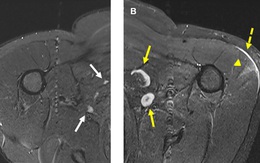

Ung thư sụn là ung thư xương phổ biến thứ 2 và chiếm khoảng 25% trong tổng số các trường hợp u xương ác tính. Bệnh này khá phổ biến ở nam giới, dễ lây lan đến các hạch bạch huyết và phổi.